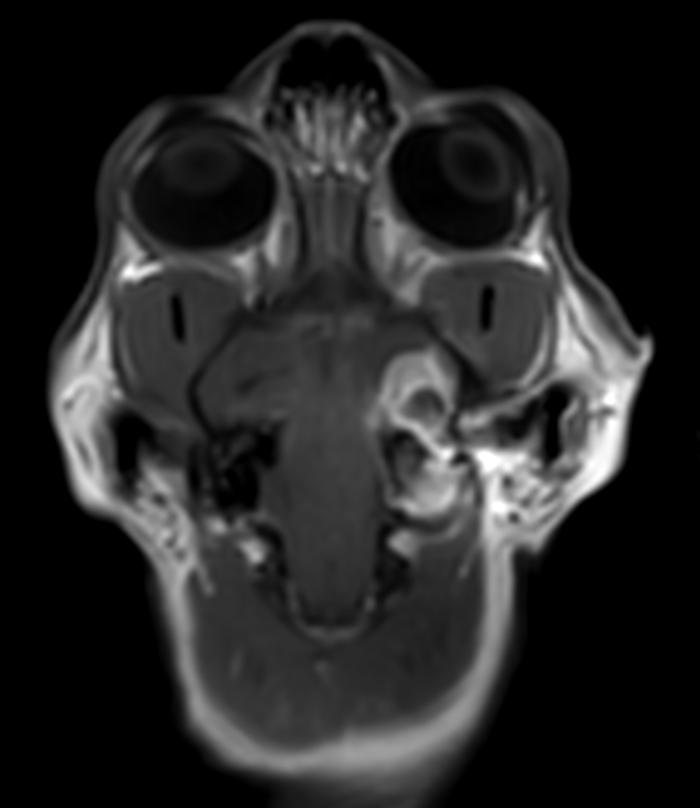

Estudio radiológico de cabeza (laterolateral derecha, ventrodorsal) y senos frontales (cráneo-caudal en flexión cervical): imagen compatible con fístula oronasal en área de pieza 204. En este momento no se aprecian alteraciones en los senos (Figura 4).

TC: efecto masa compatible con absceso, ocupando senos frontales, con osteomielitis del hueso frontal derecho, miositis y absceso en musculatura temporal derecha en contacto con hueso frontal, afectación intracraneal en área epidural del lóbulo temporal derecho con desviación de línea media de hemisferios (sin afectación de parénquima). Se observa además moderada pérdida de cornetes nasales en cavidad nasal derecha, sin secreciones asociadas y linfadenopatía regional derecha de tipo reactivo (Figura 6A-F). Se drena el contenido del absceso más superficial y se envía al laboratorio externo para su estudio microbiológico (cultivo y antibiograma).